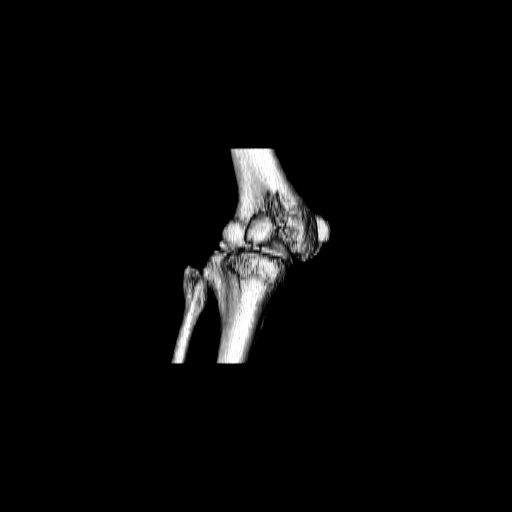

При внутрисуcтавных переломах трехмерные (3D) изображения, кроме красивого снимка, не дают полную информацию о состоянии отломков, самыми информативными являются корональные срезы на КТ и обычная длинная ренгенограмма конечности для сравнения оси конечности.

Фронтальные внутрисуставные переломы мыщельков бедра, так называемые Hoffa fracture, не частые, но встречающиеся переломы, в основном они связаны с травмой высокой энергией.

В зависимости от смещения рекомендуется сопоставление костных фрагментов с последующей жесткой фиксацией.

В вашем случае доступ будет медиальный, сопоставить развернутый медиальный мыщелок и фиксацию надо произвести в передне-заднем

направлении шурупами 4.5 мм в диаметре, углубив головку шурупов под хрящ, а поперечную фиксацию - межмыщелковыми шурупами. Желательно применить шурупы 6.3 мм в диаметре. Дополнительная Buttress technique пластина предотвратит перелом от скольжения.

Даже при сросшемся переломе мыщелка рекомендуется реконструктивная операция для предотвращения последующих варус или вальгус деформации.

Место образовавшего костного дефекта после разворота мышелка заполняется спонгиозной аутокостью. Костная пластика применяется даже

в свежем случае.

Под наркозом редрессация, ранняя разработка сустава после операции, нагрузка на конечность через 12 недель помогут удержать без коллапса

фиксацию и поможет больному восстановить функции конечности без артропластики коленного сутава.